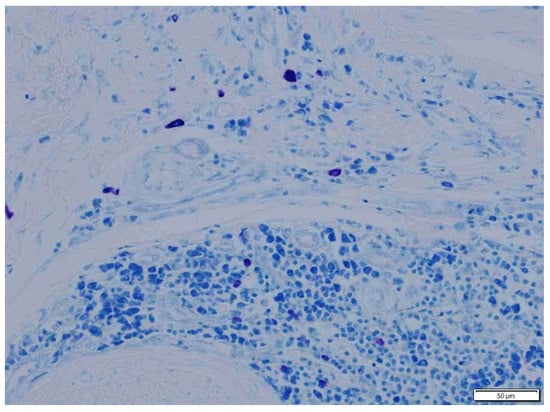

3. Results